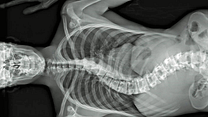

Der menschliche Körper als Konstrukt, betrachtet durch die Linse der Chirurgie: Ein Dokumentarfilm von Véréna Paravel and Lucien Castaing-Taylor, inspiriert von Andreas Vesalius' berühmter Schrift über die menschliche Anatomie "De Humani Corporis Fabrica" (1543).